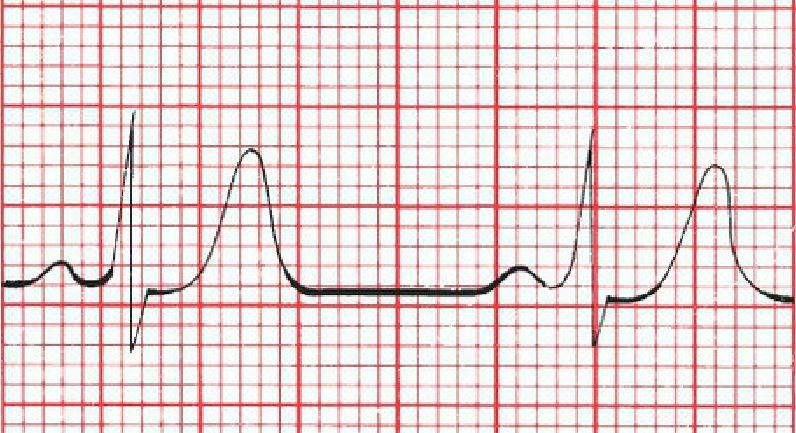

What causes this ECG?

Hypothermia. The Osborn waves are very prominent.